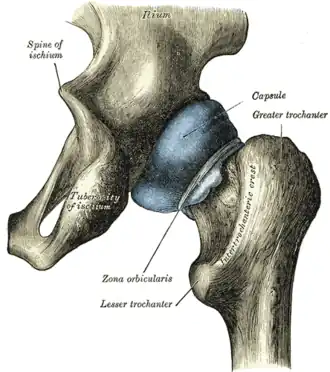

Capsule of hip-joint (distended). Posterior aspect. | |

It surrounds the neck of the femur, and is attached, in front, to the intertrochanteric line; above, to the base of the neck; behind, to the neck, about 1.25 cm above the intertrochanteric crest; below, to the lower part of the neck, close to the lesser trochanter.

The circular fibers, zona orbicularis, are most abundant at the lower and back part of the capsule, and form a sling or collar around the neck of the femur.